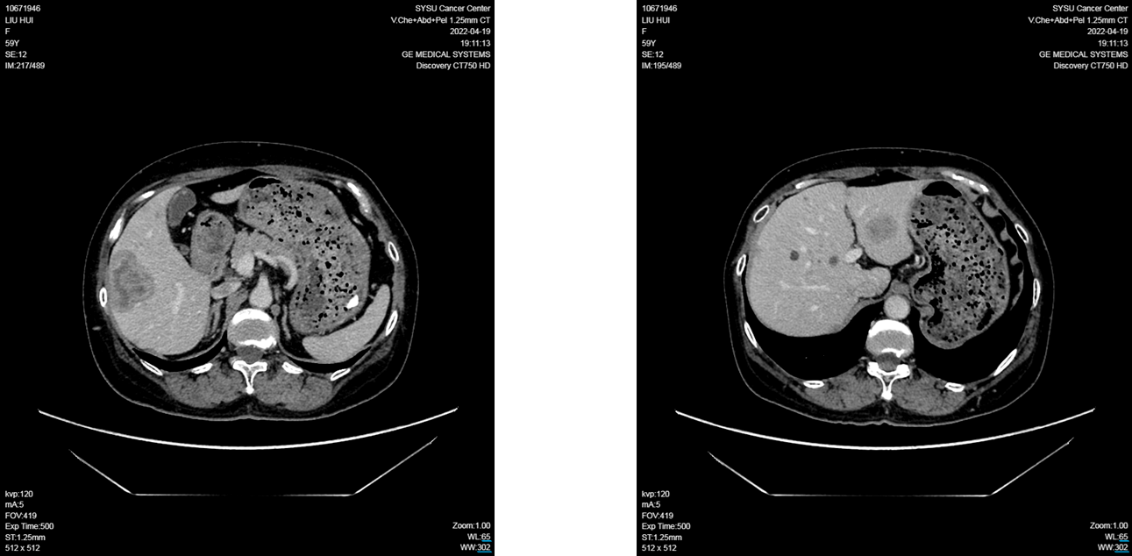

2022年2月患者于外院复查MRI提示肝脏多发转移病灶,最大病灶约5×3×3.8 cm 。患者转至中山大学肿瘤防治中心进一步诊治 ,并于3月行肝穿刺活检 。病理结果证实为乳腺癌肝转移 ;转移灶IHC结果为ER (90%+)、PR (5%+)、HER2 (1+)、Ki-67 (20%) 。NGS检测提示,明确存在PIK3CA基因: p.H1047R 突变 。

2022年4月27日,患者入组WO41554临床试验,接受“伊那利塞(GDC0077)/安慰剂+哌柏西利+氟维司群”的三靶点联合治疗。仅2个周期后(2022年6月),影像学即显示肝转移灶明显缩小;后续多次评估均维持部分缓解(PR)。